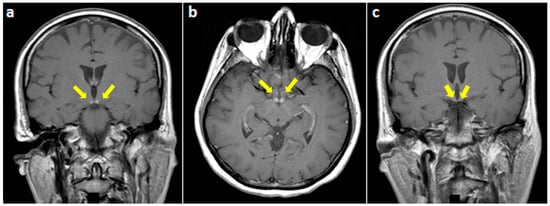

On examination, she was alert and cooperative, but disoriented to time and place, and unable to recall three objects on a mini-mental status exam. For the latter exam, the score was 18/30 on admission. Other cognitive domains were intact. In addition, cranial nerves as well as motor, sensory, and cerebellar functions were normal. The patient underwent brain MRI imaging which revealed normal T1, T2, and fluid-attenuated inversion recovery (FLAIR) sequences (Figure 1). However, T1 gadolinium-enhanced sequences demonstrated an isolated enhancement of the mammillary bodies (Figure 2).

Figure 1. Fluid-attenuated inversion recovery brain magnetic resonance (MR) images (coronal view), at the level of (a) mammillary bodies, (b) third ventricle, and (c) midbrain, showing a normal magnetic resonance imaging (MRI) signal in these regions.